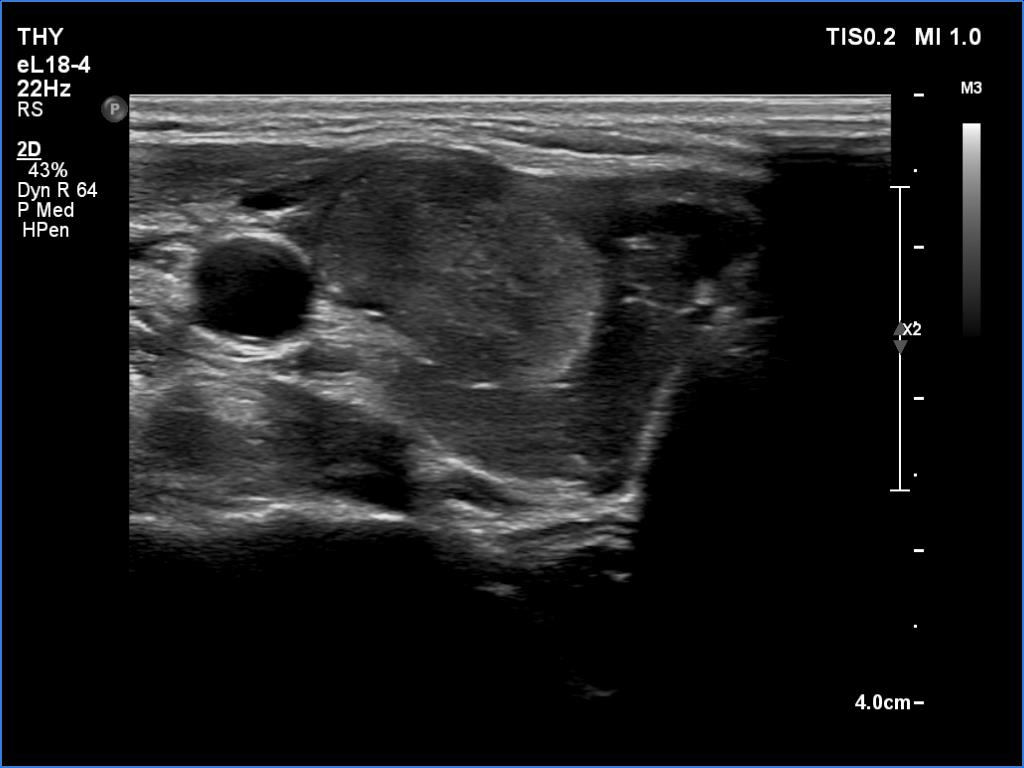

According to the palpable mass in the right submandibular area, there was a heterogeneous lesion which has hypoechoic and echonormal parts. The mass had irregular margins and showed vascularity. The distance between the submandibular mass and the thyroid was more than 35 mm.